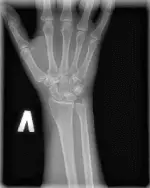

Рентгенографія променевозап’ясткового суглоба може проводиться в передньо-задній і бічній проекціях, з обов’язковою оцінкою стану кісток зап’ястя (ладьєвидної, півмісяцевої, тригранної).

З патології променевозап’ясткового суглоба найчастіше буває травма – перелом променевої кістки в «типовому» місці. Особливе значення при цьому має розпізнавання внутрішньосуглобових переломів.

У цьому істотно допомагає рентгенографія суглоба.